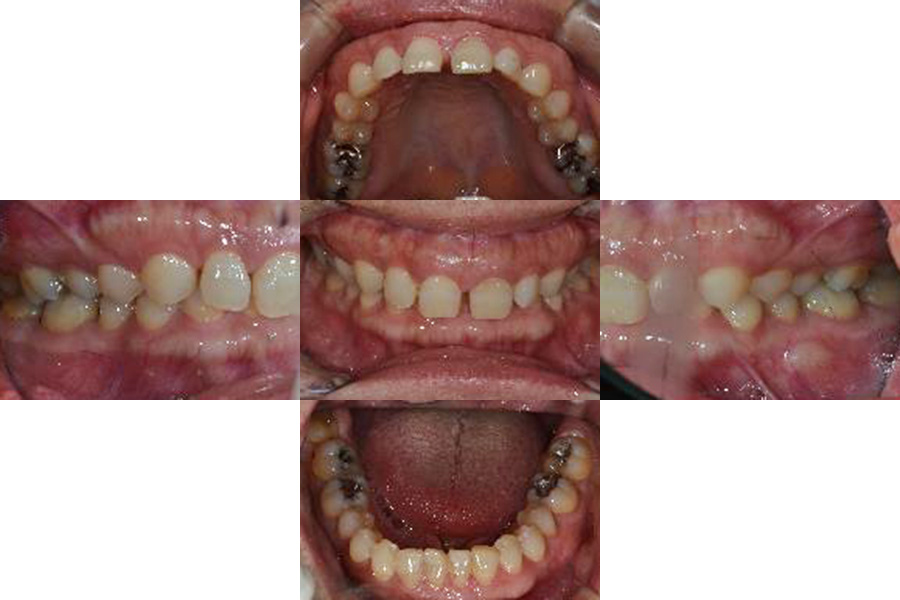

| 術前 |

![]() |

年齢:33歳

主訴:前歯の黒ずみがきになる。奥歯に穴が開いている気がする。

初診時の診断と治療方針

医療面接、レントゲンや写真より、歯並びの問題と将来的に噛み合わせから顎関節症状がでてくる恐れがあると診断できました。そのため、矯正治療を含めた咬合治療をしていくことになりました。